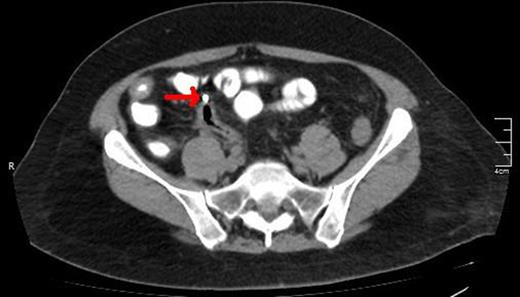

A CT view of the same patient showing the lower edge of the biliary stent perforating the sigmoid colon (red arrow).